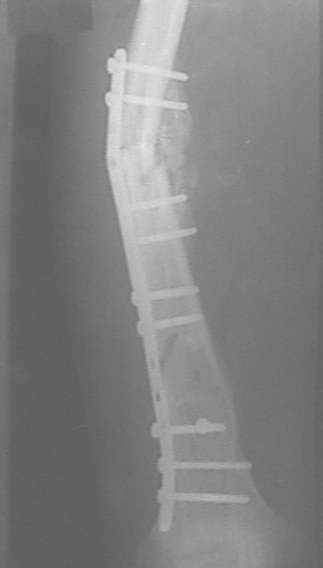

Александр Николаевич, к сожалению больной не является на контрольные осмотры. Я последний раз видел больного, когда прошло 7 месяцев после операции БОС. У него все хорошо. Каких либо жалоб и ограничений в нагрузке нет. Высылаю снимки до операции и последние снимки.

Сергей Зырянов

Новосибрская область

г Куйбышев